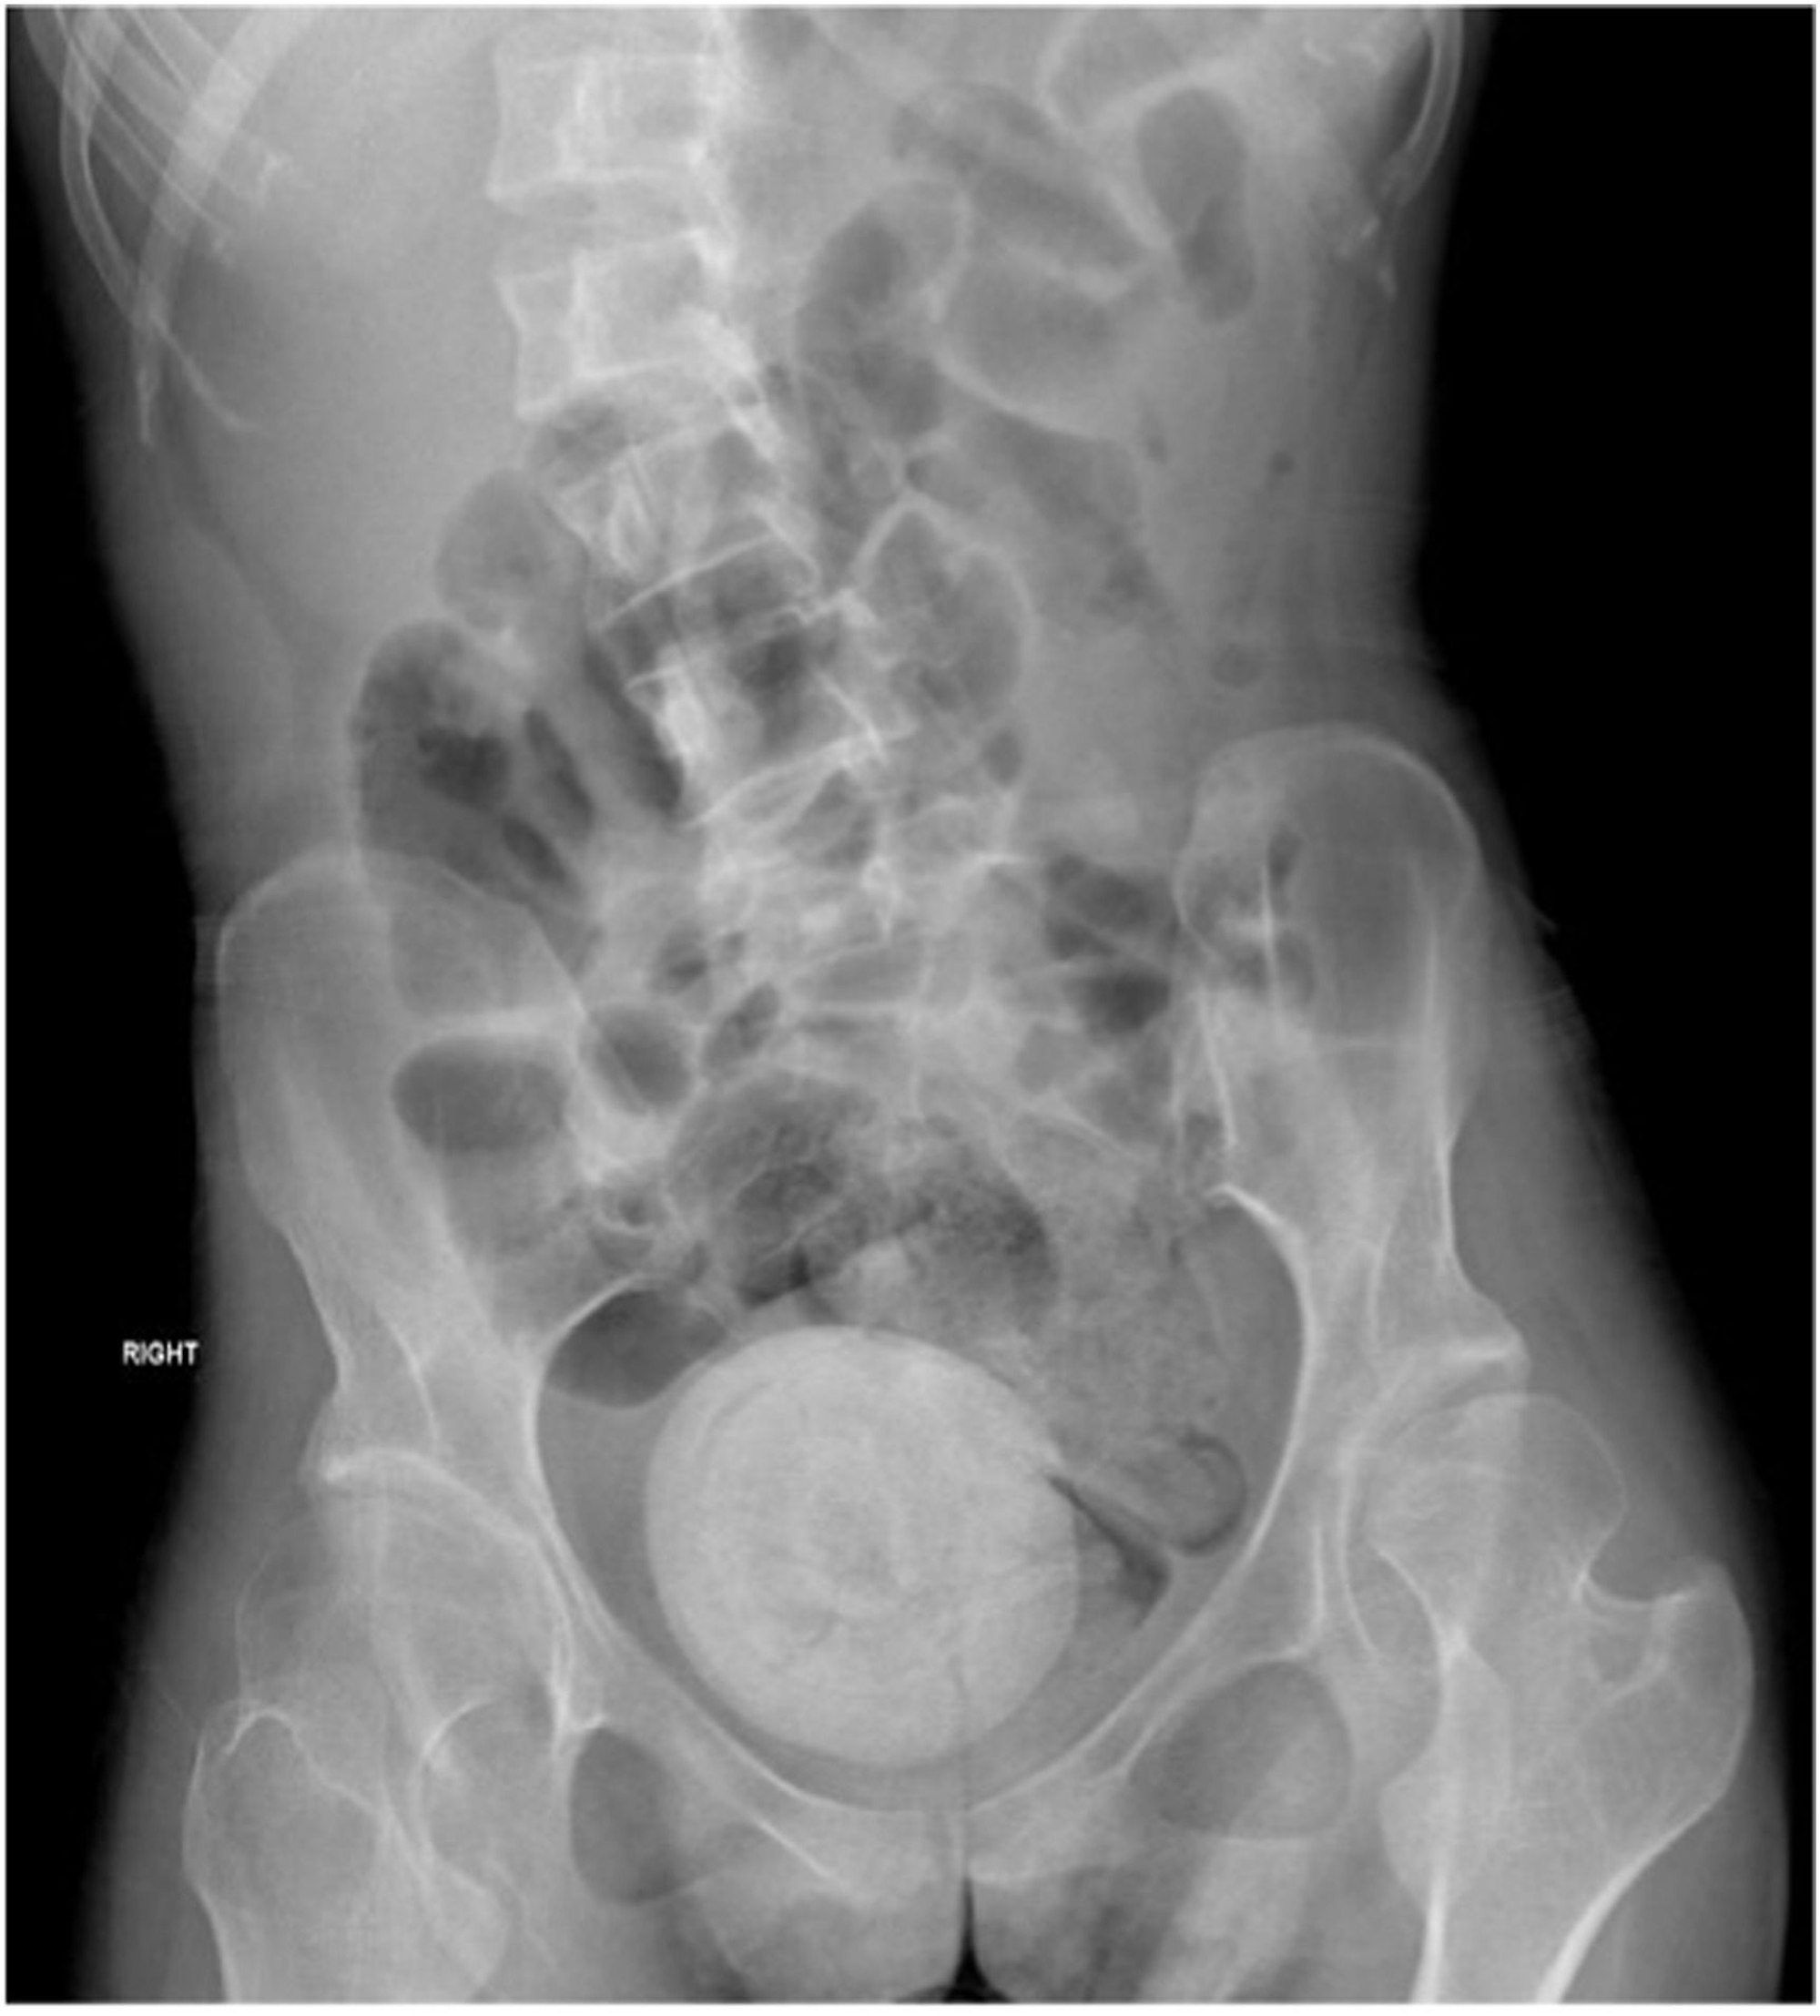

Die Röntgenaufnahme zeigt den großen Fremdkörper im Unterleib der Patientin.

Der neun mal zehn Zentimeter große Fremdkörper wurde zunächst mit einem Laser in kleine Teile zerschossen, wie die Fachzeitschrift „Urology case reports“ berichtet. Nach sechs Wochen wurden die einzelnen Steine in einer dreistündigen Operation entfernt.

Noch ungewöhnlicher ist jedoch die Größe des Vaginalsteins, der laut Ärztinnen und Ärzten die Größe einer Orange hatte. Der Stein entstand wohl durch die Stauung von Urin in der Vagina. Die Frau leidet an einer Muskelerkrankung und Inkontinenz, was die Bildung eines solchen Vaginalsteins begünstigt.